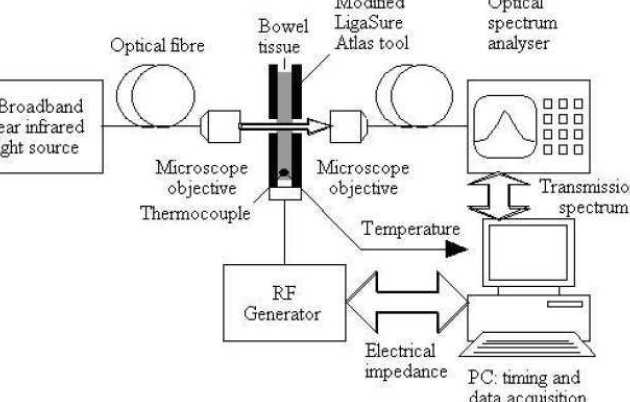

Timmy Floume, Richard Syms, George Hanna, Ara Darzi (St Mary’s Hospital)

Radio frequency (RF) tissue fusion is a novel method of tissue approximation that can seal tissue without the need for sutures or staples, based on tissue transformations induced by Joule heating and mechanical pressure. RF delivery must be controlled and optimised to obtain a reproducible, reliable seal. At present, tissue impedance is used for feedback during RF blood vessel sealing. We have developed a method of real-time optical measurement to improve understanding of the tissue modifications induced by RF fusion. Near infrared transmission spectroscopy has been used for dynamic acquisition of the tissue attenuation spectrum, and the modified Beer-Lambert law has been used to extract optical parameters. Simultaneous temperature measurement shows that tissue coagulation alters scattering losses and that tissue dehydration induces changes in the water absorption band near 1450 nm wavelength.

|

|---|

| Experimental arrangement |

|

|---|

| Water absorption band in pig bowel tissue |